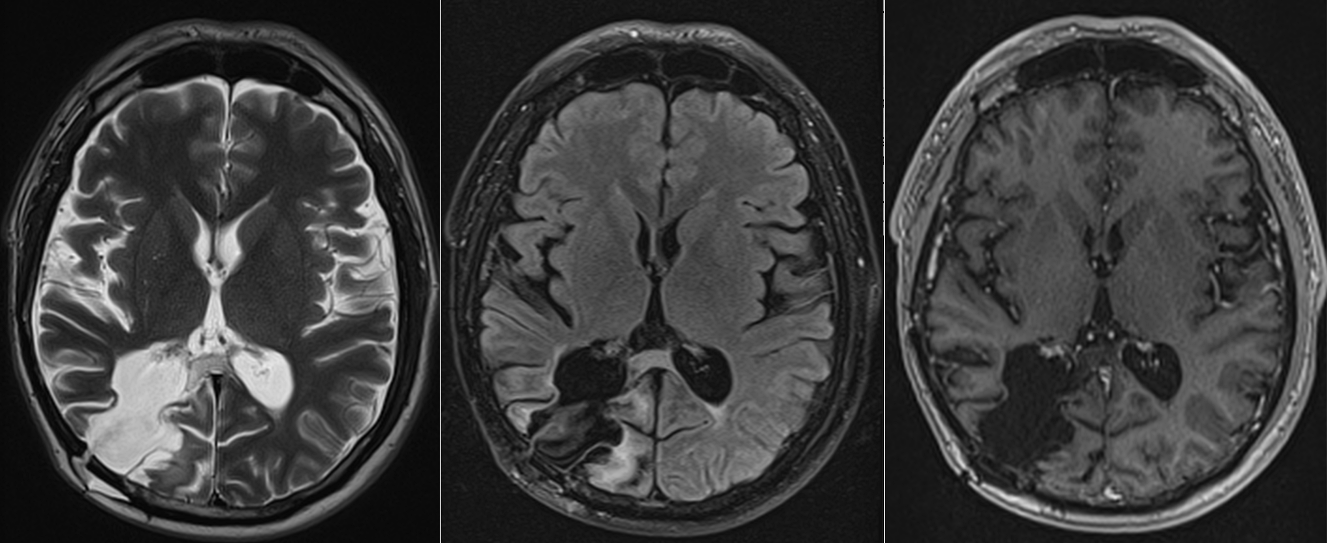

Investigația prin RMN cerebral a clarificat situația: exista o tumoră cerebrală situată în regiunea occipito-temporală dreaptă, o zonă a creierului implicată în procesarea informației vizuale și în recunoașterea fețelor.

Operația a decurs în condiții bune, iar tumora a fost rezecată într-o proporție foarte mare. Analiza microscopică a confirmat diagnosticul de astrocitom anaplazic (grad III) – o tumoră glială cu potențial agresiv.